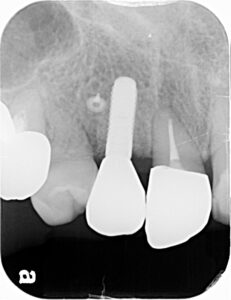

そこからインプラントが生着するのを待って上部構造を作成します

骨がなくてインプラントができないようなケースでも、このように骨を造ることでインプラントが可能になります